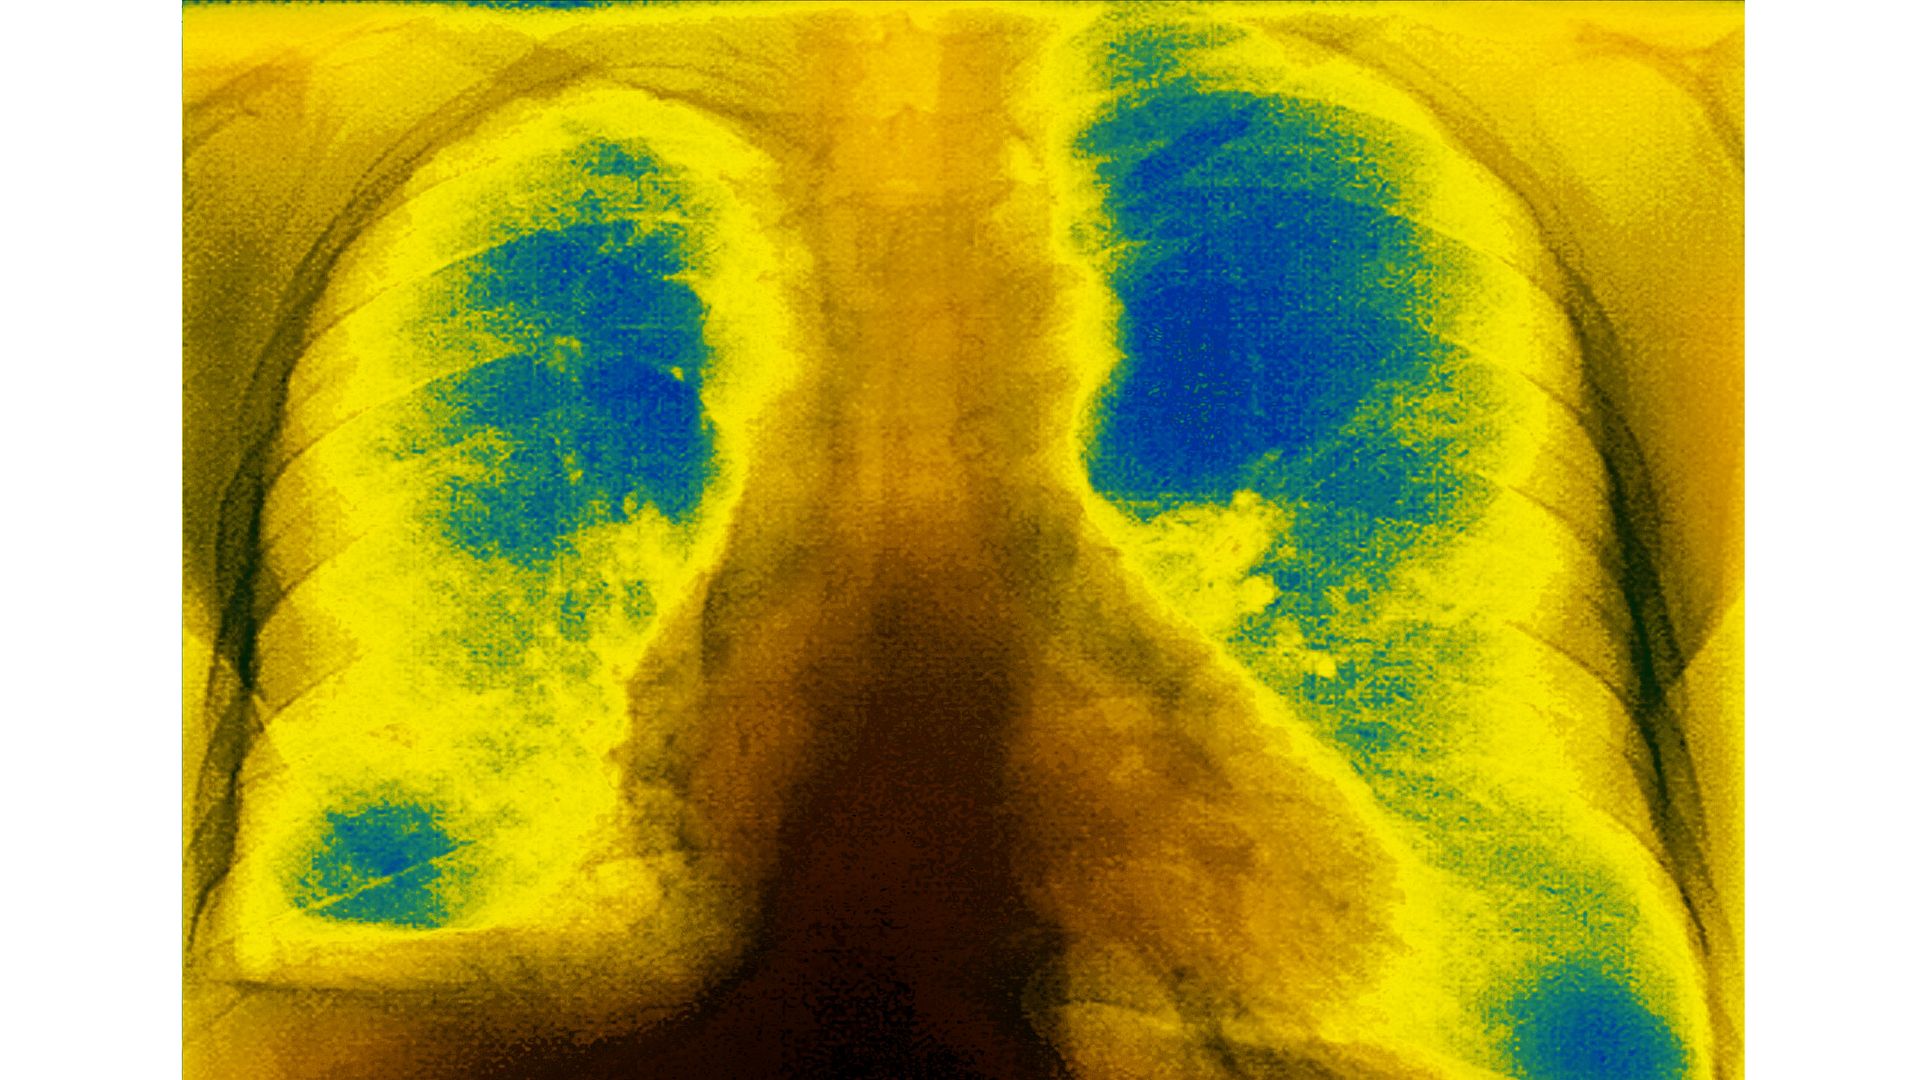

- Cystic fibrosis is a chronic, progressive and frequently fatal genetic disease that primarily affects the respiratory and digestive systems of children and young adults.

- Patients over the age of 12 with at least one F508del mutation of the inherited disease will be eligible for the therapy. In clinical trials, patients who received Trikafta experienced significant improvements in lung function, STAT News reports.